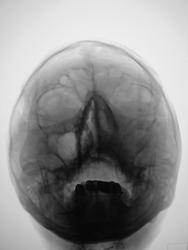

похоже на гиперпластический. В лобной пазухе виден уровень жидкости.

А я плохо вижу костные стенки левой гайм. пазухи...."оно" проростает..

Согласен, невиден медиальный контур левой гайморовой пазухи, надо исключить деструкцию

затемнение не совсем гомогенное, возможно солидные образования в верхнечелюстной пазухе. Во фронтальной не вижу достоверных данных за уровень-что можно было бы трактовать за жидкость. Для этого надо уточнить положение пациента при исследовании, а так же рентгенография пазух лобной кости в боковой проекции в вертикальном положении пациента. Имея только этот снимок - Левостороний гемисинусит. А вообще рекомендовал бы томографию, ну честно-все встало бы на места.

Снимок сделан в вертикальном положении.